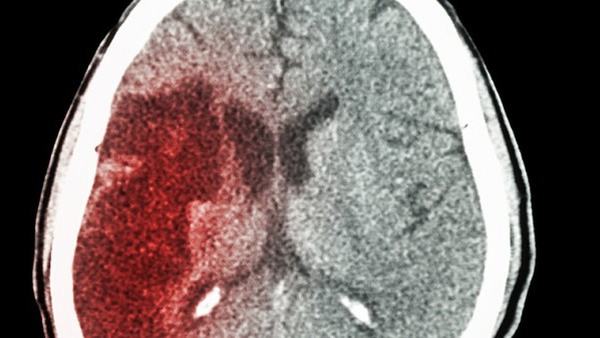

在临床上,对于可疑肺脓肿患者,一般会进行临床检查和影像学检查。临床检查包括体温测量、肺部听诊、咳嗽咳痰的观察等。影像学检查主要是通过X线、CT等影像学技术检查肺部,并可以明确肺脓肿的位置、大小和数量。